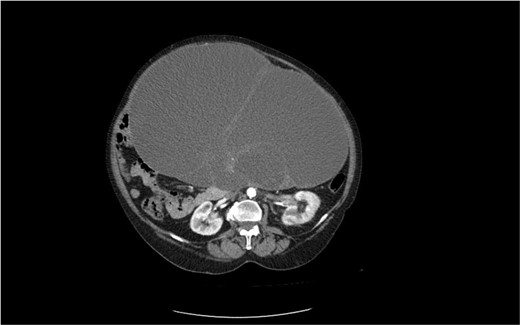

A 75-year-old woman with a complaint of heaviness in the abdomen with gradually increasing dimensions, as well as heaviness in the groin areas with pronounced constipation for several years, was consulted by a surgeon. Abdominal ultrasound revealed a large cystic formation with a hypoechoic appearance with isoechoic components in it with size of ~198 mm/d, compressing adjacent distended intestinal loops. To the left of it, a smaller structured cystic zone ~5 cm/d was visualized. Subsequent computed tomography (CT) of the abdomen and pelvis with contrast revealed a well-demarcated large cystic mass on the right of the pelvis, tracing cranially preaortic, retroperitoneally and reaching the level of the epigastrium, measuring 150/210/138 mm/d, thin-walled with homogenous contents and an adherent appendix to the wall. Numerous thin septa were visualized inside (Fig. 1). A second finding with a cystic structure is present on the left of the small pelvis with a size of 69/85/100 mm/d in contact with the main formation along the lower lateral and a contour of 7 cm/d. There is a herniation of the right lateral surface of the bladder into the right inguinal canal, a transitional herniation of the sigmoid to the left inguinal canal. Computed tomography confirm an ovarian cystadenoma on the right. Laboratory indicators did not give a deviation. A joint decision was made with a gynecologist to perform a laparotomy with hysterectomy (Fig. 2), bilateral adnexectomy, and appendectomy. Intraoperatively, the finding was consistent with that described by CT. The histology result revealed a serous ovarian cystadenoma on the left and fallopian tube with an abudance of cystically transformed Walthard’cell nests. The same changes were also described in the right fallopian tube, mucinous ovarian tumor with borderline malignancy, and appendix fibrinous purulent periappendicitis. The patient had no postoperative complications and was discharges on the seventh postoperative day.

CT image of a large ovarian mucinous cystadenoma of the left ovary.